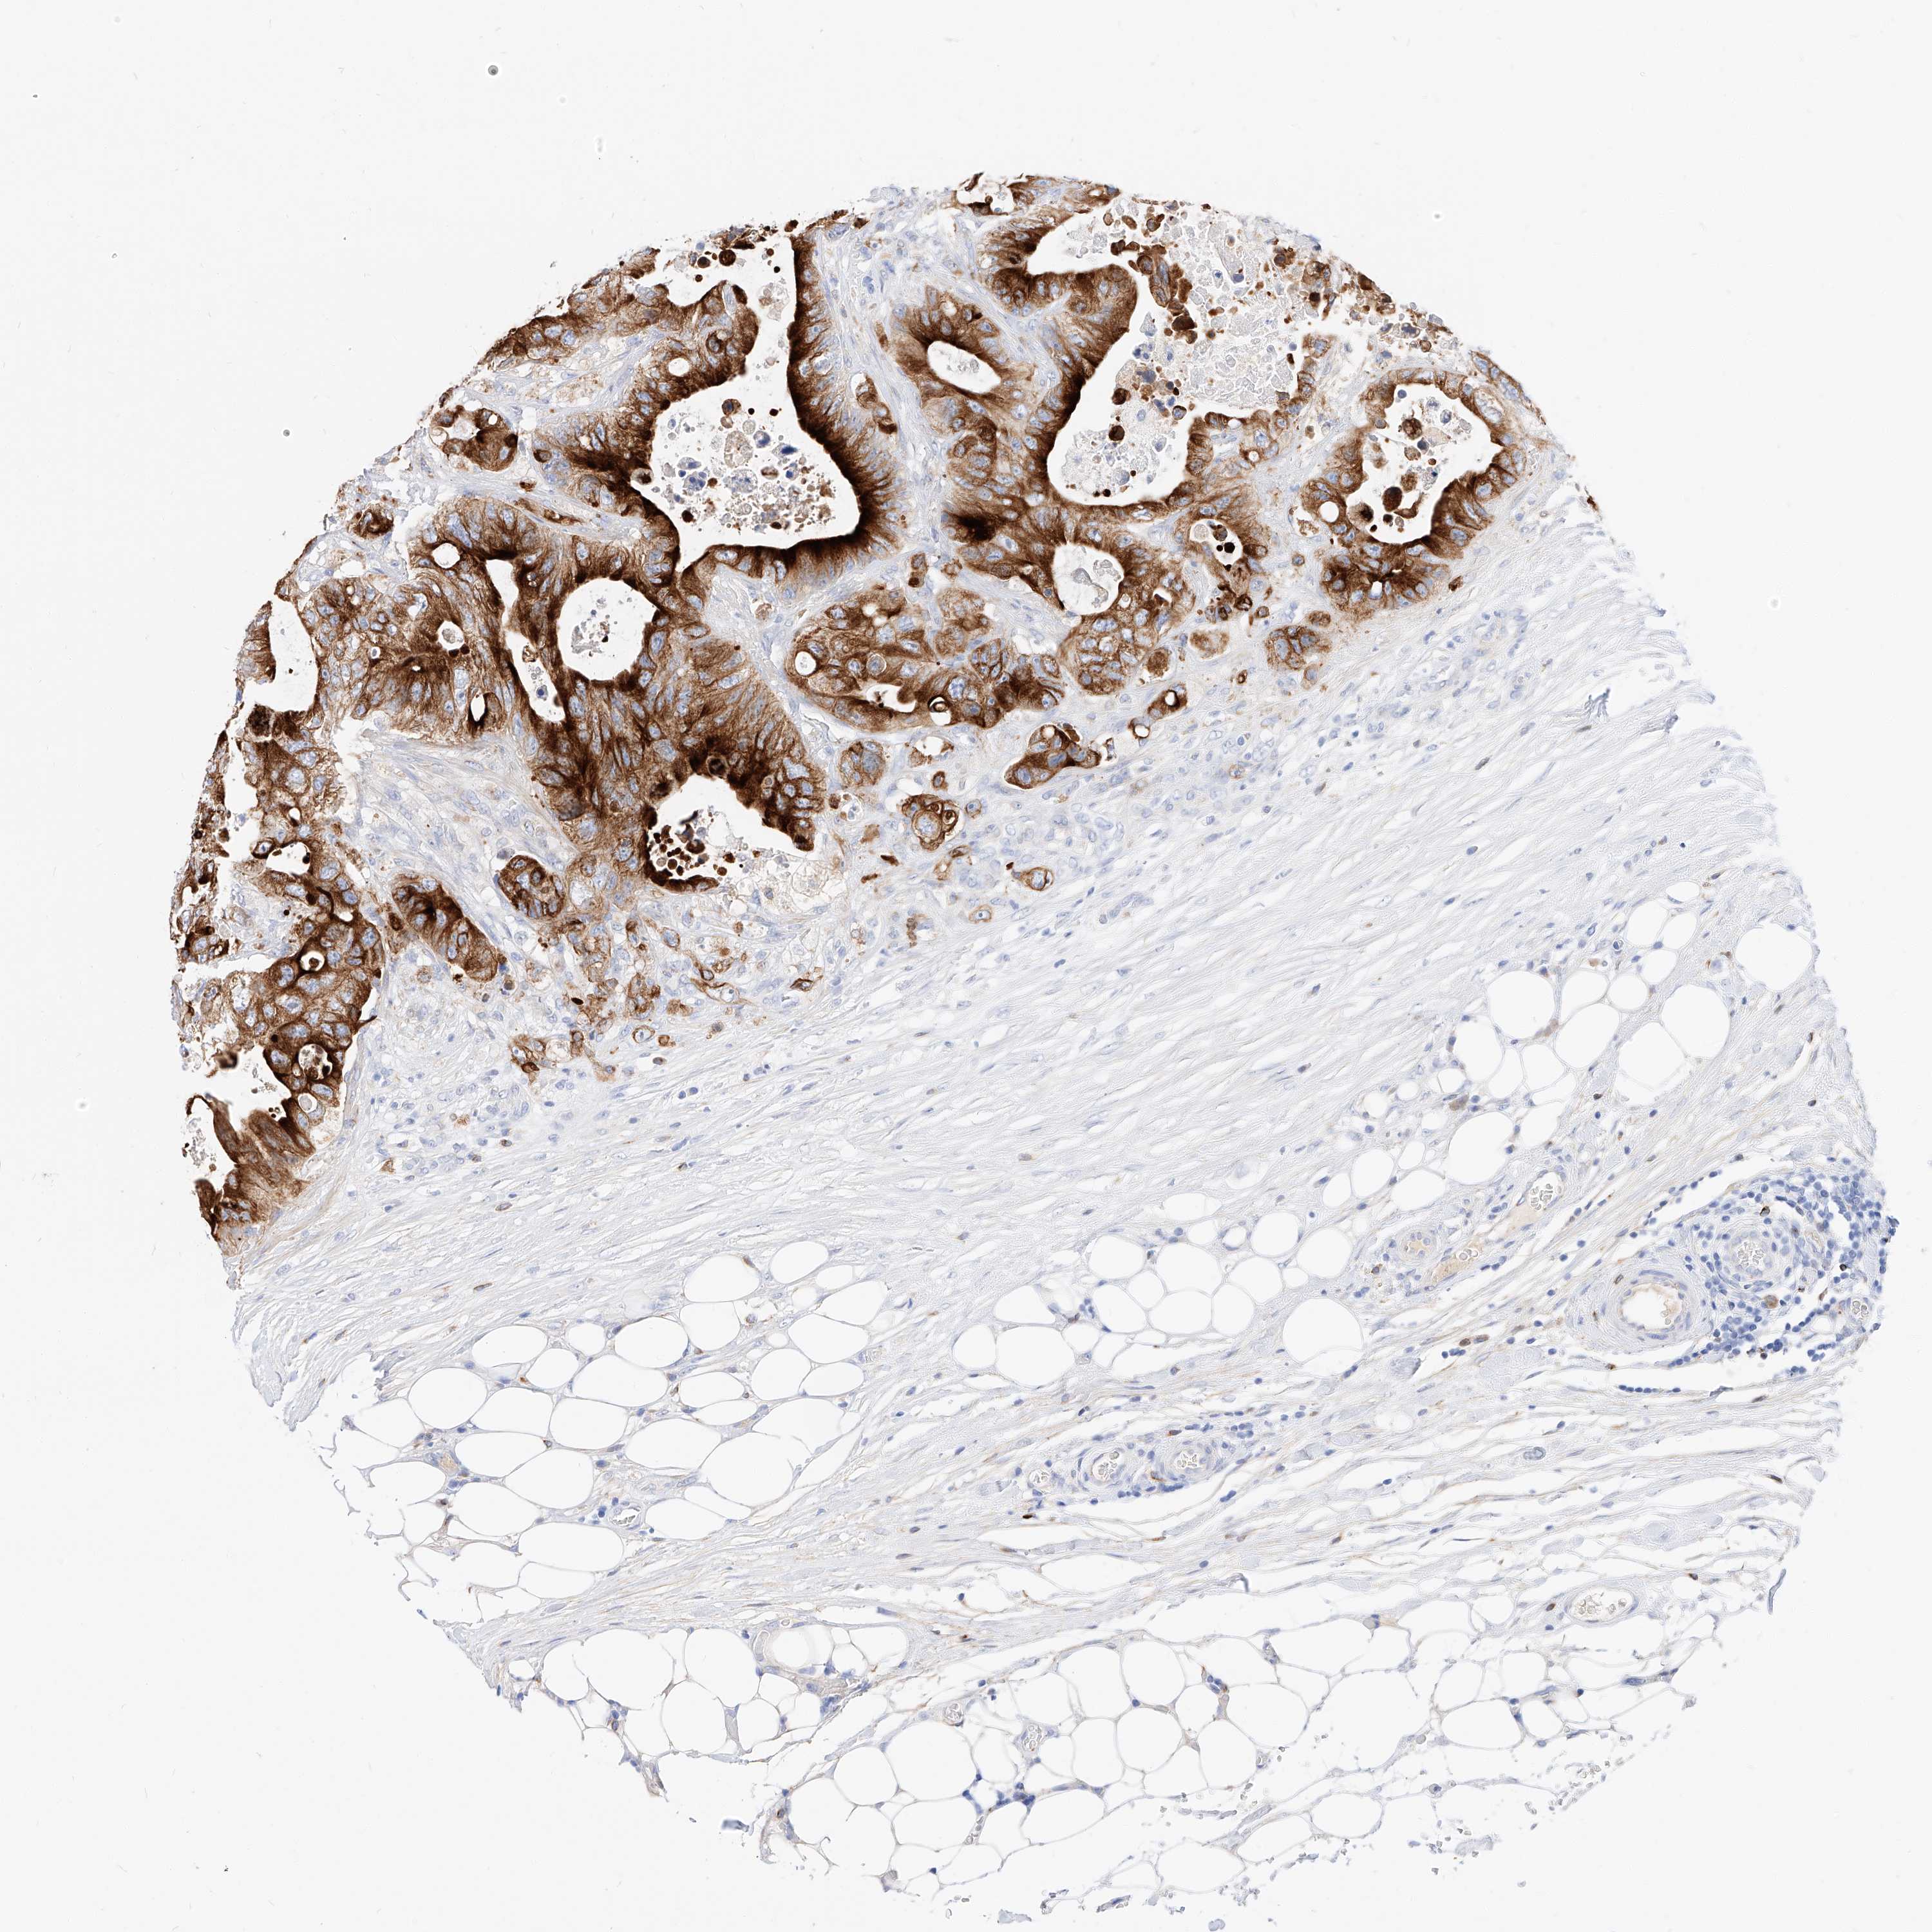

CANCER COLORECTAL CANCER Show tissue menu

Colorectal cancer

Human cancer

Colon adenocarcinoma